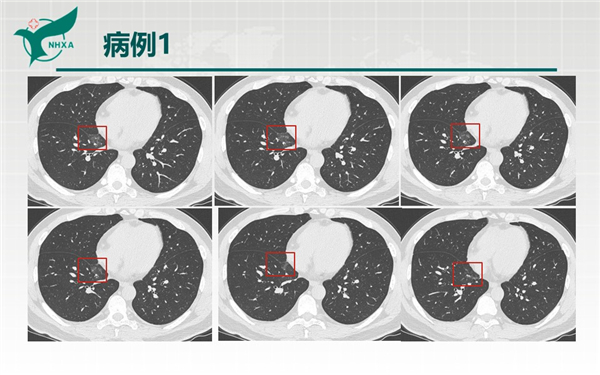

幻燈片2.jpg